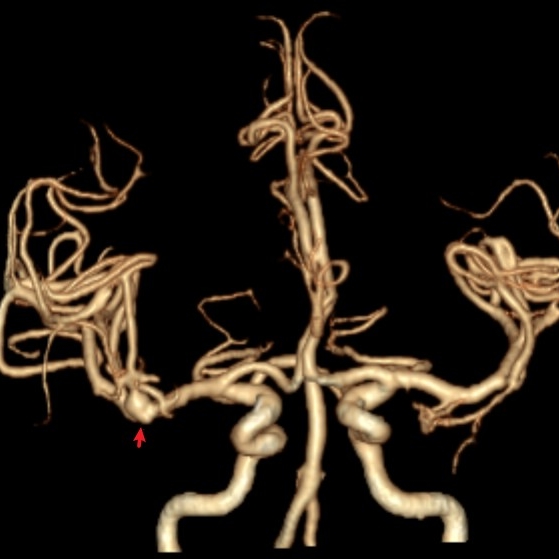

病例一为77岁女性患者,既往高血压病史。因“突发剧烈头痛伴恶心2天”前来清华大学附属垂杨柳医院急诊科就诊。头颅CT检查提示蛛网膜下腔出血,头颈动脉CTA提示右侧大脑中动脉M1段分叉处宽颈动脉瘤。神经外科脑血管病介入团队急诊为患者实施了全脑血管造影术(DSA),造影显示动脉瘤不规则,可见子囊,宽颈,主要累及下干。团队采取了支架辅助弹簧圈栓塞术,患者颅内“不定时炸弹”被成功拆除。动脉瘤达到致密栓塞,载瘤动脉通畅。住院半个月后顺利出院,无神经功能障碍。

▲CTA显示右侧大脑中动脉分叉动脉瘤